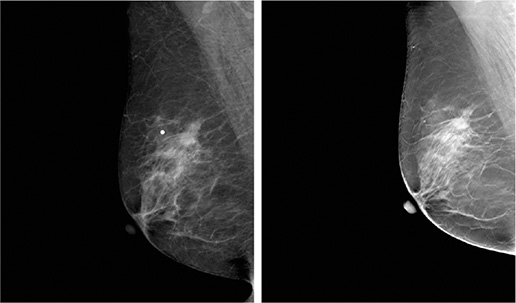

Wstęp Cyfrowa mammografia stała się nowym standardem we wczesnej diagnostyce raka piersi [1, 2]. Jednak mimo wszystkich korzyści wynikających z jej stosowania, metoda ta nadal ma ograniczenia. Badania pokazują, że ok. 22% złośliwych nowotworów, zwłaszcza w piersiach o kompozycji gruczołowej, pozostaje niezdiagnozowanych [3]. Jedną z przyczyn może być efekt nakładania się tkanek – zmiany lub inne struktury anatomiczne mogą…